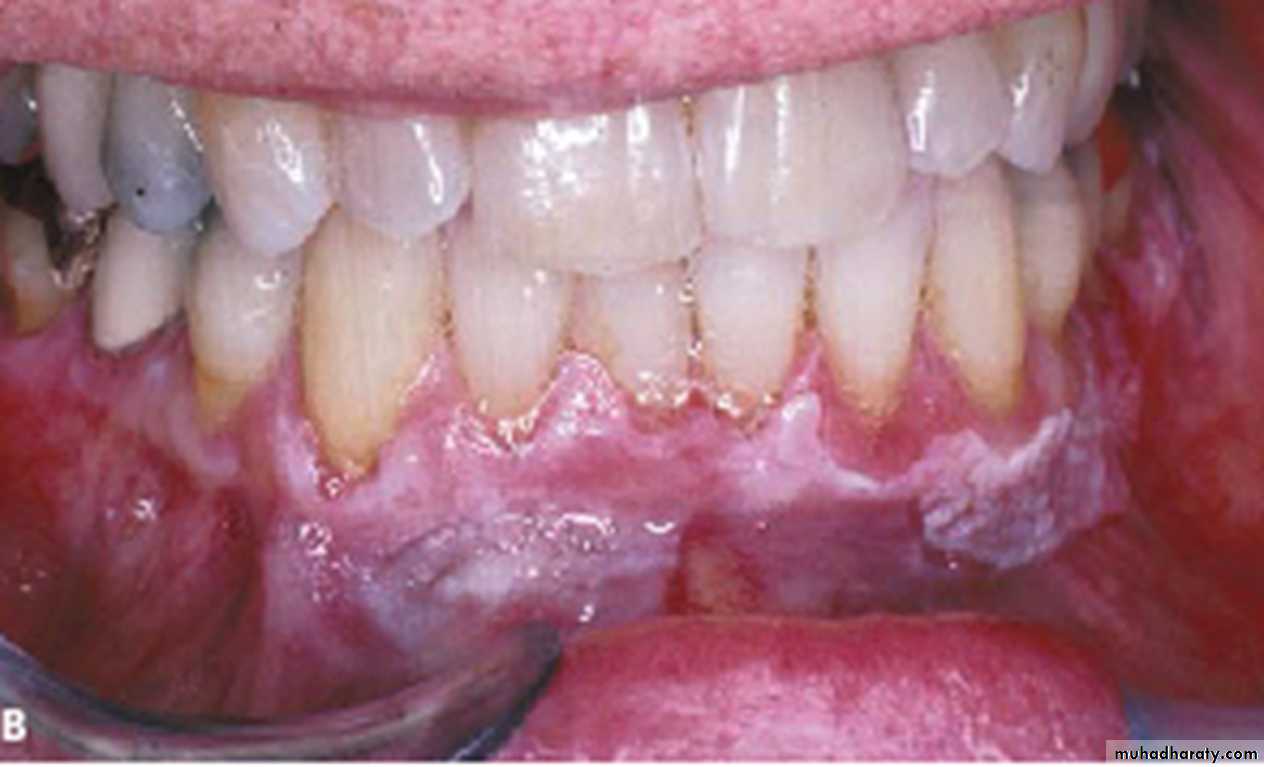

Proliferative verrucous leukoplakiaDiffused, thick, white plaque with verrucous surface involving the labial mandibular gingiva and adjacent vestibule